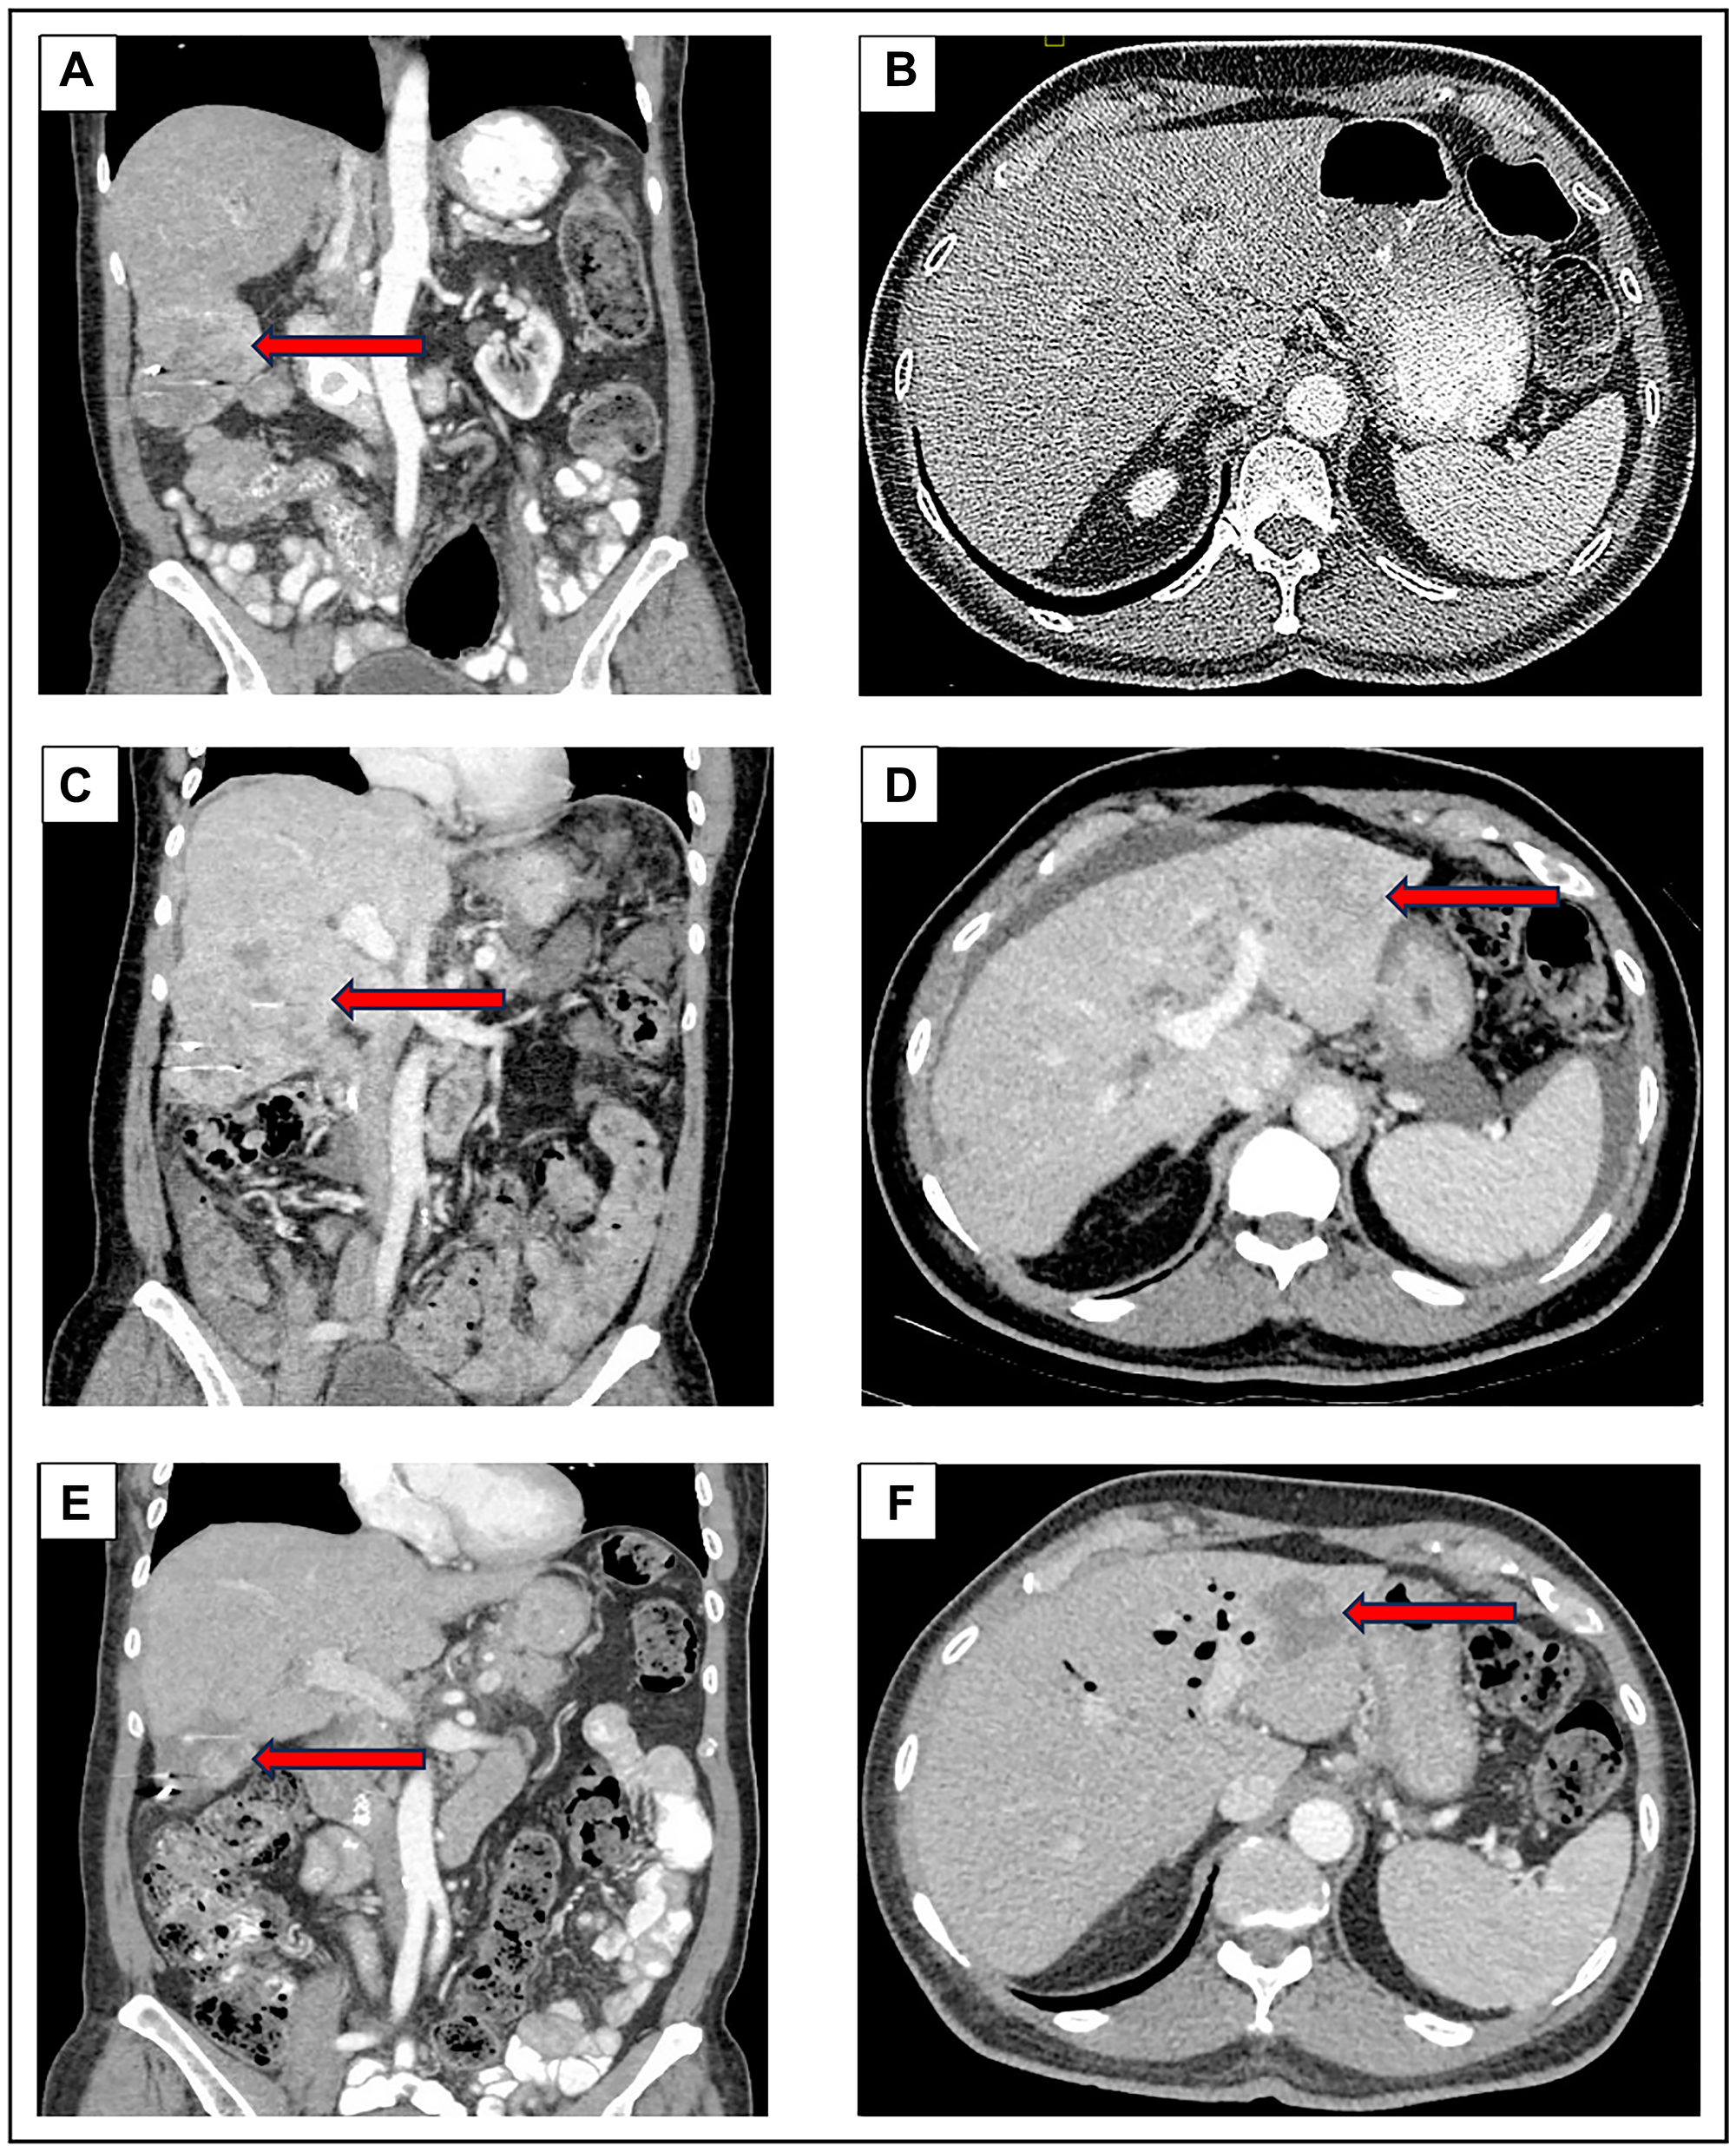

CT Scan on initial presentation to our institution in October 2022 (A, B) demonstrated a right lobe liver lesion measuring 8.2 cm in greatest dimension. In April 2023 (C, D), after six months of treatment with sotorasib, there was an increase in the right lobe liver lesion to 10.2 cm along with a new left lobe lesion measuring 5 cm. In July 2023 (E, F), after four cycles of pembrolizumab, the right lobe liver lesion reduced in size to 5.7 cm and the left liver lobe lesion decreased to 3.5 cm.

The patient was discussed in our multi-disciplinary conference and the recommendation was to initiate an immune checkpoint inhibitor (ICI) considering the tumor’s squamous histology. He received the first dose of pembrolizumab in May 2023. In July 2023, the patient was hospitalized for pancreatitis: investigational studies were unremarkable for common etiologies, hence it was likely an immune-related adverse event from the pembrolizumab. Symptoms resolved shortly after admission and steroids were not administered, but pembrolizumab was held for one month until lipase levels normalized and his activity level improved to his baseline of ECOG performance status of 1. A subsequent CT scan in July 2023 demonstrated a significant reduction in both hepatic masses, with the right lobe mass measuring 5.7 cm, decreased from 10.2 cm three months prior, representing an approximate 88% reduction in tumor volume (Figure 3). He has since resumed pembrolizumab and completed six cycles at our institution at the time of last follow-up in September 2023, after which returned to his prior institution to continue therapy.